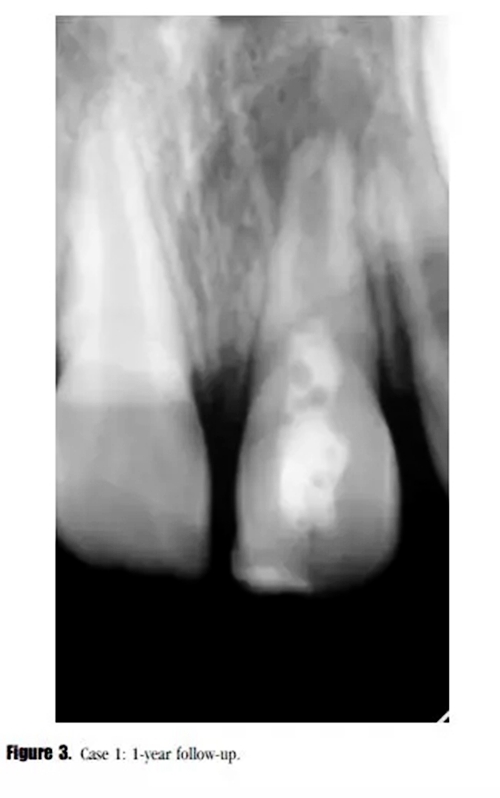

在第12個月的評估中,叩診與捫診又輕微不適。在臨床牙冠上未發(fā)現(xiàn)充填材料與牙體的縫隙以及隱裂線,探診深度正常。我們采用了一種細菌加強型封閉劑來預防再感染。影像學評估顯示,根尖周投射影增大、牙根停止發(fā)育,以及近中根管內(nèi)壁的輕微吸收。(圖3)